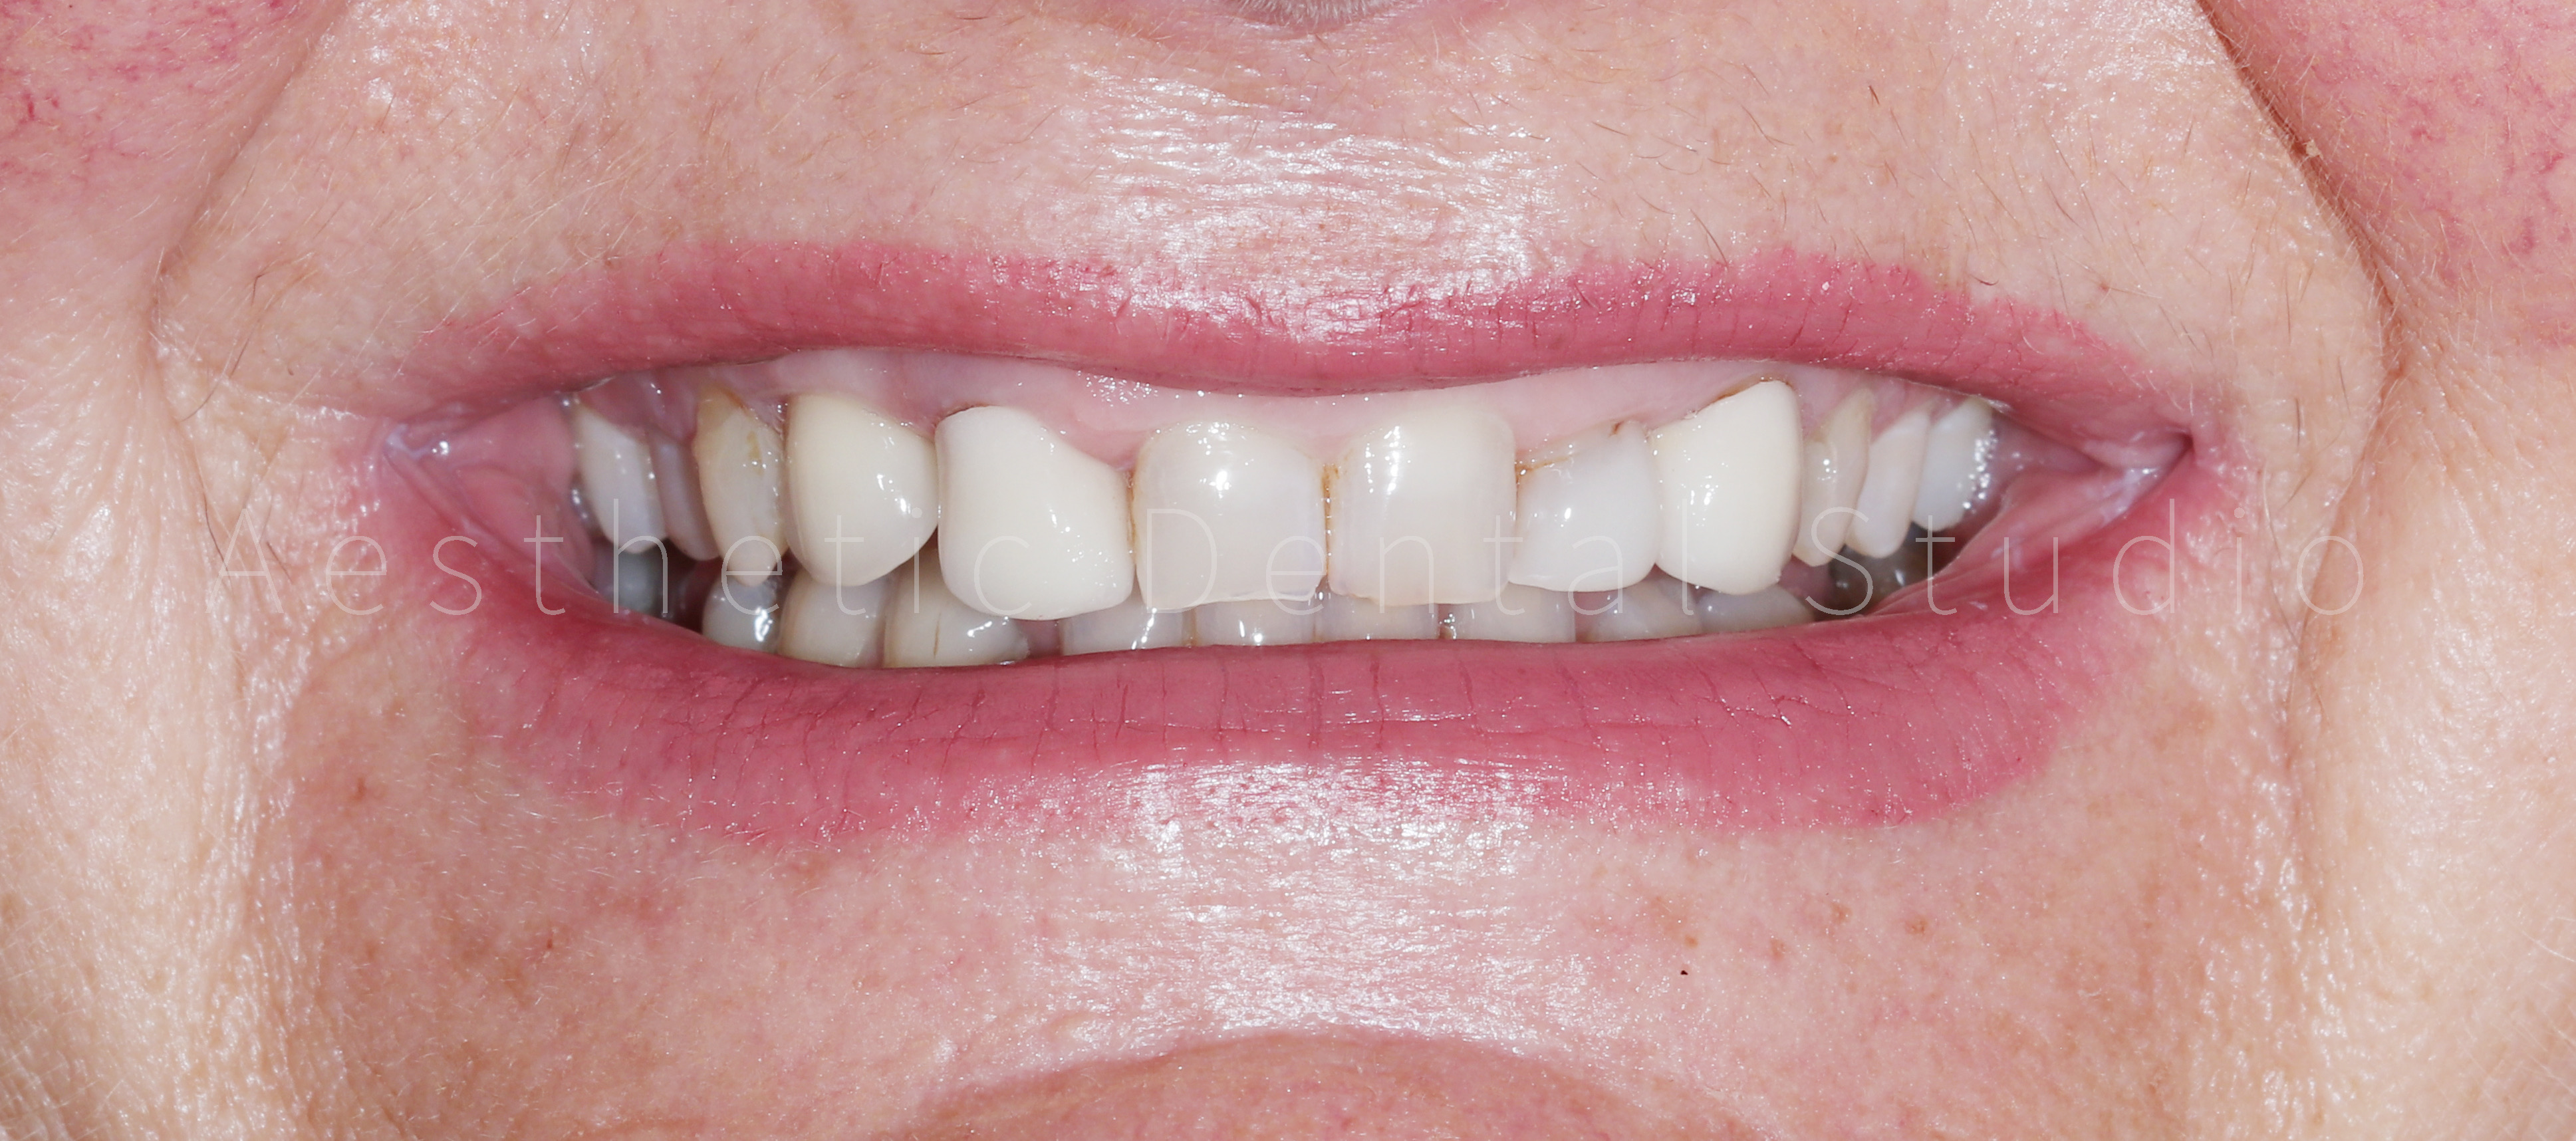

Ασθενής από τη Δυτική Ευρώπη επισκέφθηκε το Aesthetic Dental Studio κατά τη διάρκεια των διακοπών της στην Καλαμάτα, με βασικό στόχο τη βελτίωση της αισθητικής του χαμόγελού της. Η αρχική εικόνα παρουσίαζε ανομοιομορφία στο σχήμα και το χρώμα των προσθίων δοντιών, φθορά των κοπτικών άκρων και παλαιές αποκαταστάσεις που αλλοίωναν τη συνολική αρμονία του χαμόγελου. Η ασθενής ε πιθυμούσε ένα φυσικό αλλά αισθητικά άρτιο αποτέλεσμα, διατηρώντας την αυθεντικότητα των χαρακτηριστικών του προσώπου της.

Το τελικό χαμόγελο ήταν φυσικό, φωτεινό και αρμονικό, αναδεικνύοντας τα χαρακτηριστικά της ασθενούς, χωρίς υπερβολές. Η θεραπεία ολοκληρώθηκε μέσα σε 10 ημέρες, συνδυάζοντας αισθητική αριστεία, λειτουργική σταθερότητα και άριστο χρονοπρογραμματισμό. Η ασθενής αναχώρησε από την Καλαμάτα με ένα εντελώς ανανεωμένο χαμόγελο, απολαμβάνοντας τη μοναδική εμπειρία ενός αισθητικού ταξιδιού οδοντιατρικής φροντίδας στην Ελλάδα